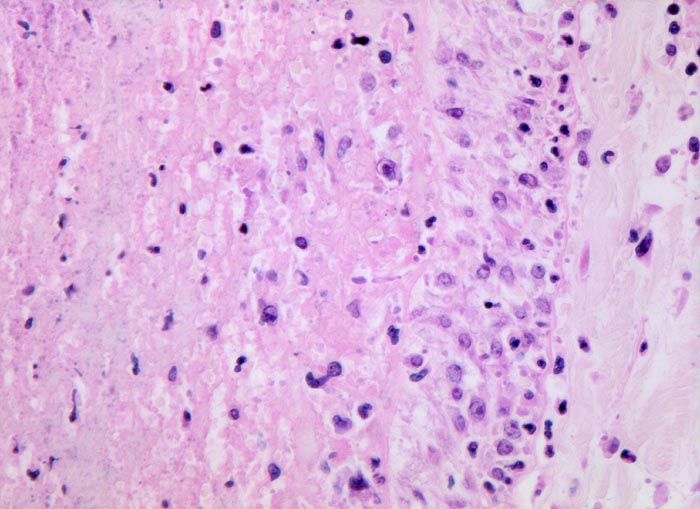

PathoPic – image database / PathoPic ID 3564 - frische Lungenembolie

frische Lungenembolie

Rechts im Bild die Gefässwand. Links im Bild der Embolus bestehend aus Fibrin und zerfallenden neutrophilen Granulozyten. An der Grenze zwischen Gefässwand und Embolus hat sich noch kein Organisationsgewebe ausgebildet. Man sieht an dieser Stelle jedoch zahlreiche eingewanderte Monozyten.

Tiefe Beinvenenthrombosen bei metastasierendem Prostatakarzinom. Koronare Herzkrankheit.

Histologie

320